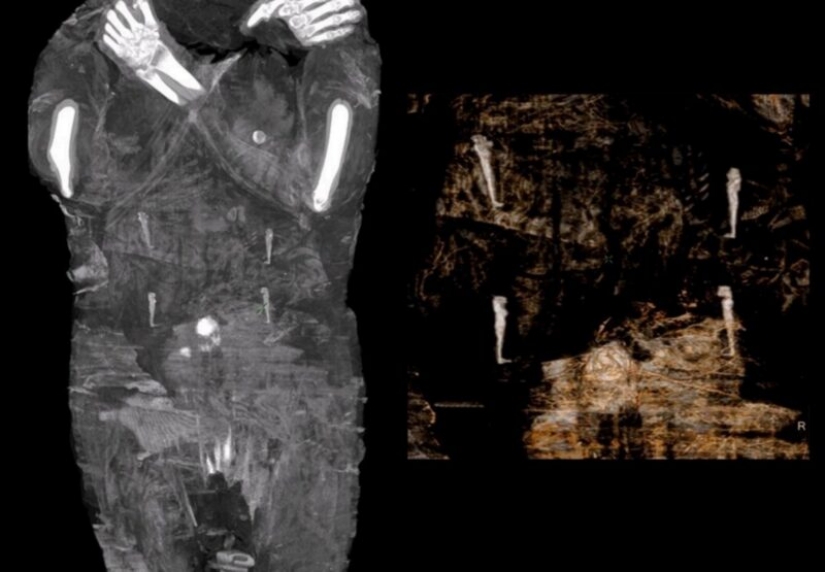

For the new study, scientists decided to scan the body and were surprised to find that in fact, a woman in the seventh month of pregnancy is lying in the coffin.

According to scientists, this is the only known case of a well-preserved pregnant Egyptian mummy. They determined that the woman was between 20 and 30 years old. And the size of the fetal skull suggests that she was somewhere between 26 and 28 weeks pregnant.